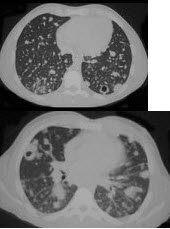

6、单项选择题

患者轻微咳嗽,实验室检查嗜酸粒细胞升高,影像学检查如图,两次检查时间相距8小时,最可能的诊断为()

A.双下肺肺炎

B.军团菌肺炎

C.金黄色葡萄球菌肺炎

D.支原体肺炎

E.过敏性肺炎